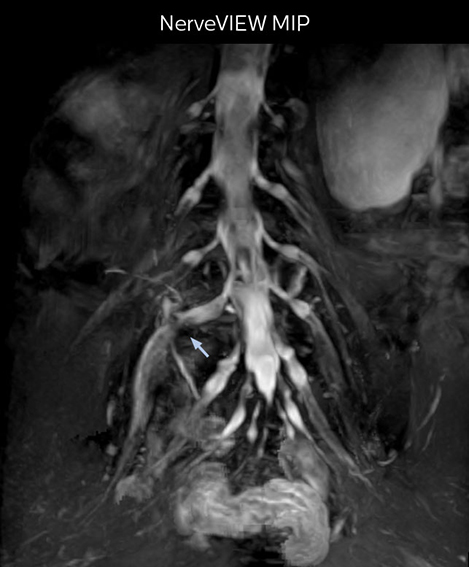

“In such case, we would then browse through axial T2-weighted MR images slice by slice and mentally reconstruct the actual situation based on both radiculography and MRI. Fortunately, NerveVIEW can now very well show nerve courses and presence of nerve compression or edema in one single image series.” “We have often seen NerveVIEW directly depict details of the nerve compression that were not observed by radiculography. Therefore, we think that with NerveVIEW we can reduce the number of invasive examinations, especially for some patients with lumbar plexus symptoms.”

“Before NerveVIEW, diagnosis by MRI alone was sometimes difficult, unless there was a strong suspicion based on clinical symptoms,” says Shoji Yabuki, MD, DMSc, Orthopedic surgeon at Fukushima Medical University School of Medicine. “This is why we routinely perform selective lumbosacral radiculography (nerve root block) and x-ray in such cases. However, radiculography can only depict nerves as far as the contrast agent reaches. When a nerve is distorted by compression, the contrast agent will not pass through this compressed area, preventing us from evaluating the full nerve compression.”

The key concept in MR neurography, Dr. Yabuki stresses, is the ability to directly visualize spinal nerves, versus inferring the presence of pathology indirectly. “Before NerveVIEW, we estimated compression of the nerve by looking for the presence or absence of fat signal on other MR images,” he says.

“For example, in sagittal images, when the presence of fat is observed in the intervertebral foramen, it suggests that there is a margin around the nerve. Similarly, the absence of fat indicates that the nerve is being compressed. So, we used to deduce nerve compression indirectly. With NerveVIEW, however, we can observe the condition of the nerves directly, regardless of the presence or absence of fat. We always prefer such direct observation of anatomy over having to make an inference about it.”

“Although symptoms of typical disc herniation and atypical hernia are very similar, the actual site of herniation is different. It is therefore important to characterize the nerve’s condition both inside and outside of the intervertebral foramina. “Conversely, if we see no abnormality in NerveVIEW, we can assume at least that there is no severe condition that requires surgery. Like this, it can help us avoid unnecessary surgery. NerveVIEW can have a tremendous impact in this way.”

“NerveVIEW is really useful for those cases where a nerve disorder is strongly suspected based on the clinical examination but our regular MRI images do not show any findings. These atypical herniations and spinal canal stenosis, occurring in 5% to 15% of the total lumbar herniation/stenosis cases are our main target when using NerveVIEW,” says Dr. Yabuki.